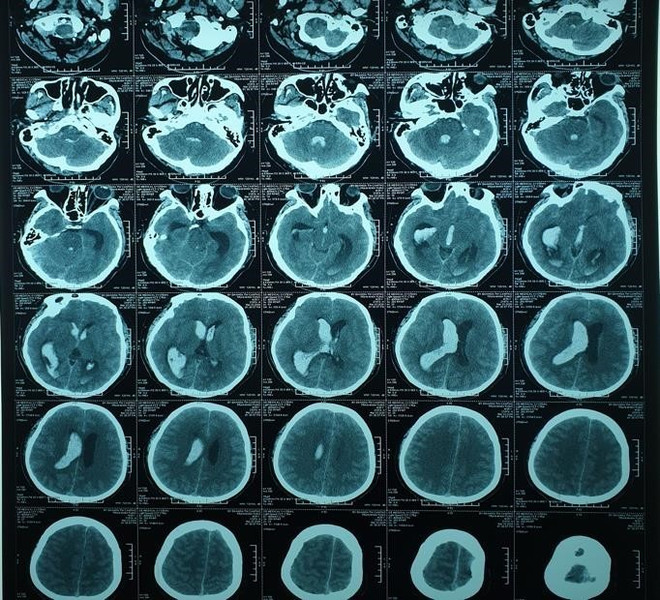

CT扫描结果表明,患者脑出血并破入脑室,导致脑室扩张。

一个星期后,脑室血肿明显减少,患者退烧,开始有知觉。20天后可以睁开眼睛,听从命令,呼吸良好,没有发烧症状。4月19日,患者生命体征平稳,情况良好,转入康复治疗阶段。